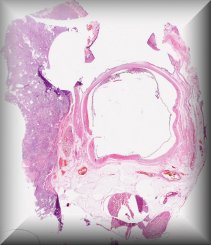

Fiona Roberts (Glasgow): 9 year old female with buphthalmos secondary to congential glaucoma. Protocol |